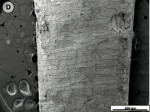

When the tooth slices with the ex vivo-grown salivary biofilm were examined under the scanning electron microscope, they were colonized by luxuriant biofilm covering the entire surface (Figure 2A, Figure 2B, Figure 2C). The biofilms appeared to be several micrometers thick. The predominant morphotypes in the biofilms were fusiform bacteria and cocci. Several regions showed co-aggregation between the two morphotypes, which is a phenomenon of mutual dependence for nutrition and growth. The salivary-derived biofilm showed characteristics typical of a naturally occurring in vivo biofilm in the mouth. The standard jet tip treatment for 3 seconds on the tooth slices with ex vivo-grown biofilm showed extensive areas of biofilm removal in comparison with the untreated control slices (Figure 2D, Figure 2E, Figure 2F). The standard jet removed 99.99% of the salivary biofilms. The orthodontic tip treatment for 3 seconds on the tooth slices appeared to clear very extensive areas of ex vivo-grown salivary biofilm (Figure 3A andFigure 3B). Biofilm removal was observed both at the crown surface and below the cementoenamel junction. The percentage of biofilm removed by the orthodontic tip was 99.84%. Observation with the naked eye indicated that treatment of in vivo biofilm with the orthodontic tip removed significant amounts of this calcified biofilm. This was evident in SEMs, which showed the presence of clearance marks (Figure 3C) caused by the bristles associated with this tip.